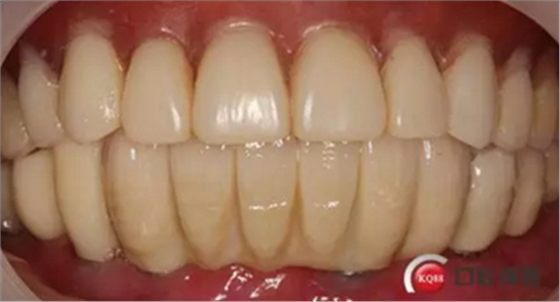

6)數(shù)字化義齒制作中心制作完成修復體臨時冠橋試戴,合適后完成最終二氧化鋯橋修復體

戴牙:試戴,拍片確定邊緣密合后調整咬合,試戴一周后患者適應,咬合良好,基臺加力30N.CM,粘接劑粘固,去除多余粘結劑,拍片確定有無粘接劑殘留,并進一步微調咬合

微笑是最美的溝通語言,患者的滿意是我們的追求

6)6個月后復查,修復體密合性均良好,修復效果符合預期,醫(yī)囑患者做好口腔衛(wèi)生預防種植體周圍炎

結果:本病例在觀察期內,種植修復獲得了良好的美觀功能的穩(wěn)定性